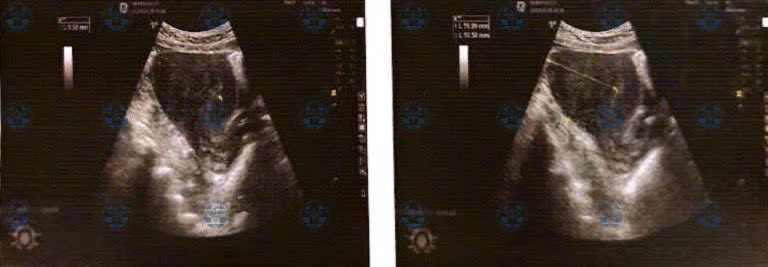

Các hình ảnh trước, trong và sau phẫu thuật